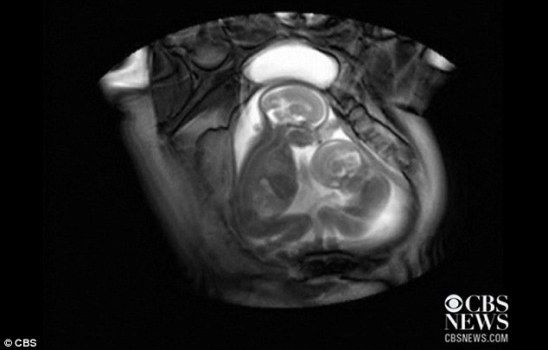

核磁共振成像技术显示,一对双胞胎在妈妈肚子里拳脚相向“掐架”

中新网12月1日电 据外媒报道,近日一段对孕期20周孕妇的核磁共振的扫描视频显示,一对双胞胎还在妈妈肚子里就开始挥动手脚 “掐架”,令人感到神奇又搞笑。

据报道,英国伦敦帝国理工学院(Imperial College)胎儿保健中心本打算用核磁共振成像仪来诊断共享一个胎盘和同一个血液供应系统的胎儿双胞胎输血症候群(twin transfusion syndrome)情况,却意外拍到了子宫中双胞胎的“大战”。

视频显示,画面右边个子稍小的胎儿在对左边稍大的胎儿挥动手脚,“拳打脚踢”,似乎打算用身体争得更多空间。而后者比较安分,也动了动嘴,缩了一下身子。